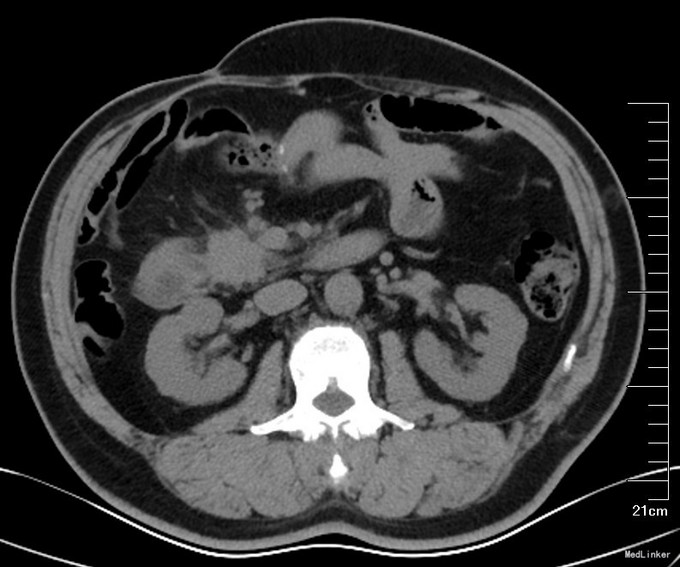

患者老年男性,72岁。以“结肠癌术后4年,烧心伴恶心呕吐6个月”为主诉入院 。现病史:患者2011年7月因肠梗阻急诊于我院行右半结肠ca根治,手术顺利,术后随访。2012年3月PET-CT(图1)提示:十二指肠前方淋巴结,2cm,考虑转移。肿瘤标志物肠癌系列升高。给予患者化疗治疗8个疗程,Xelox方案。患者肠癌系列较前有下降,但未降至正常,腹腔内淋巴结未有明确改变。患者无腹痛腹胀,无恶心呕吐。定期复查。2014-9复查CT(图2):右上腹肠管吻合口形态较前未见明显变化。十二指肠水平段前上方结节较前增大,约3.1cm×3.0cm,边缘模糊,与邻近肠壁及胰头分界不清。考虑肿物较前增大。未特殊处理,增强免疫力治疗。2015-3予以肿瘤科放疗治疗。治疗后,肠癌系列正常。CT:结节较前缩小。放疗后患者出现频繁恶心呕吐,不能进食,呕吐物为唾液,无明显食物,无营养状态下降。行胃镜检查:胃窦部溃疡,1*1cm,无幽门部变形。病理:低分化上皮内瘤变。但患者无烧心,不能除外精神因素呕吐。三个月前予以留置空肠营养管,肠内营养及经口进食。此次再次出现烧心,恶心呕吐,予以耐信口服治疗症状无好转,来诊。既往糖尿病10年。行心脏射频消融手术。